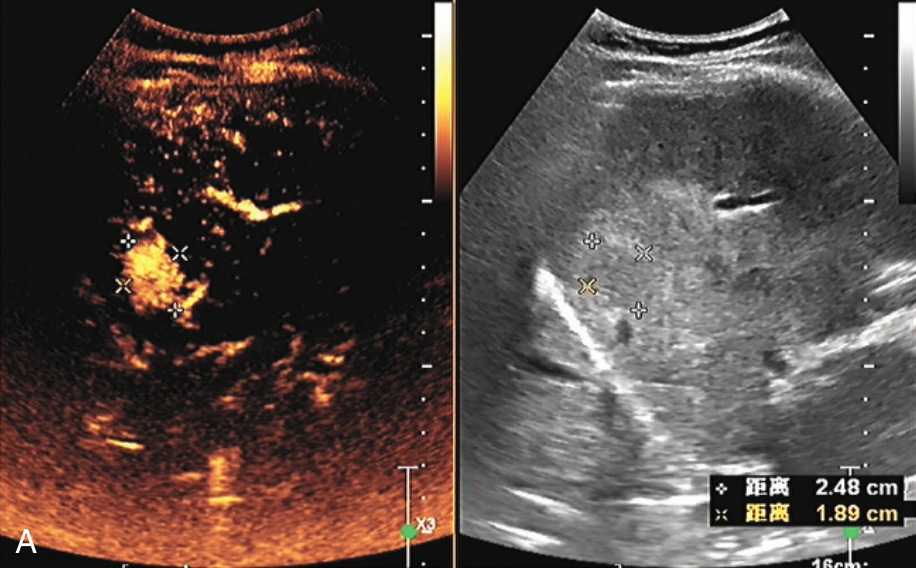

(3)彩色血流特征:

肝腺瘤的血供较丰富,病灶内部及周边可见线状或分枝状血流信号(图1-5-1B)。较大病灶周边可探及粗大迂曲的动脉血流进入病灶内,且阻力指数(resistance index,RI)<0.60。

图1-5-1 肝细胞腺瘤常规超声图像

A.肝左外叶低回声结节,内可见条索状稍高回声,边界清晰;B.CDFI示其内可见点状血流信号